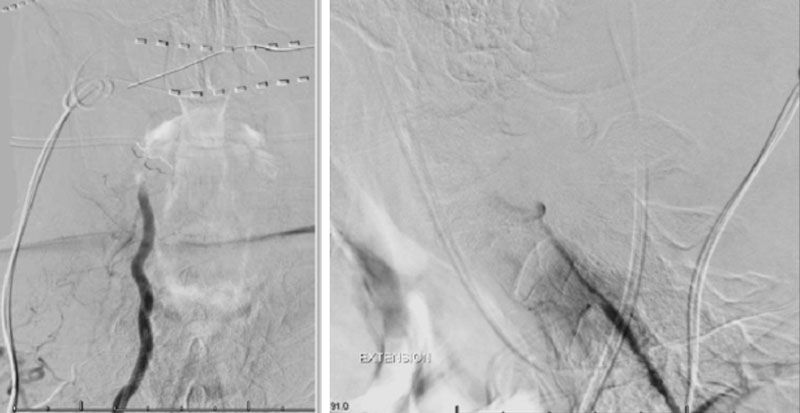

On rotation to the left, the patient experienced mild symptoms, however no significant Vertebral Artery or basilar reduction in flow was observed. On rotation to the right, the patient experiences slightly more moderate symptoms, however no significant Vertebral Artery or vascular reduction flow was observed. On hyper extension of approximately 10-15 degrees, passively performed by the patient until symptoms are reproduced, angiogram demonstrates complete occlusion of the right Vertebral Artery at approximately the C2-C1 level. (Figure 5)

It is unclear whether there is a specific bony osteophyte or soft tissue mass that is resulting in the compression. Live fluoroscopy within the neutral and extension position does demonstrate extensive arthritis and hypertrophic changes within the C1/C2 region, however specific anatomic compression is difficult to determine.